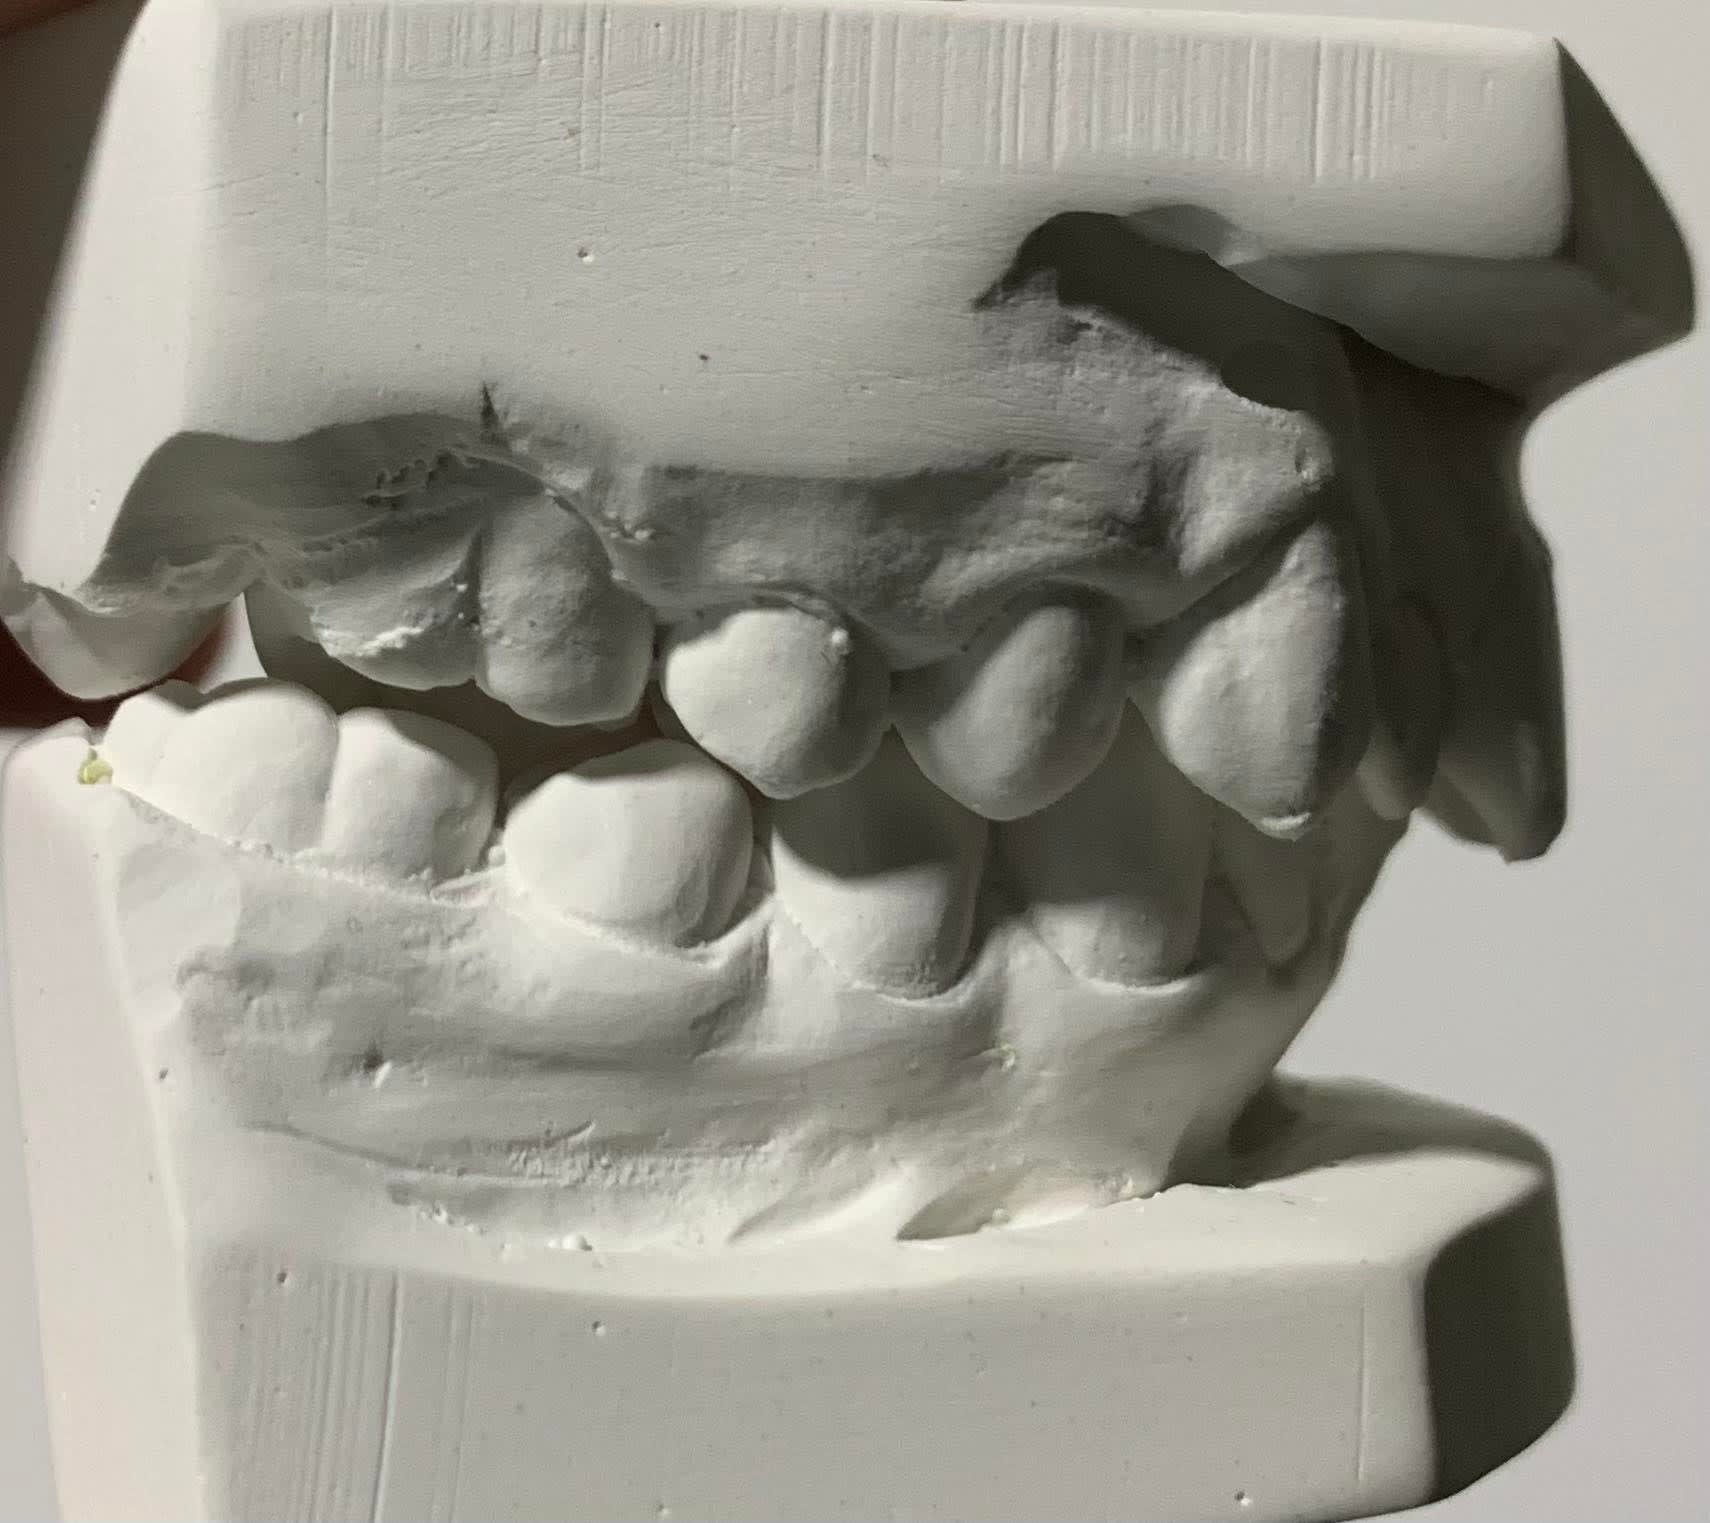

- Présence d'une incisive surnuméraire mandibulaire : responsable d'une déviation des milieux incisifs, d'un léger encombrement mais surtout camouflé par une proalvéolie importante IMPA 111°.

Bien que l'encombrement n'est pas monstrueux, je partirais quand même sur l'extraction de l'incisive la plus centrale (marquée d'une croix sur les moulages) afin d'espérer un correction de la position de l'incisive mandibulaire actuellement en proalvéolie, une légère mésialisation des secteurs postérieurs (favorable à la correction de classe II et aussi à l'évolution de la 37 actuellement retenue contre la 36). Pour la correction de la classe II soit commencer par un système carrière qui m'ouvrirait des petits espaces pour traiter l'encombrement maxillaire puis poursuite par un traitement multiattache avec utilisation d'élastiques de classe II.